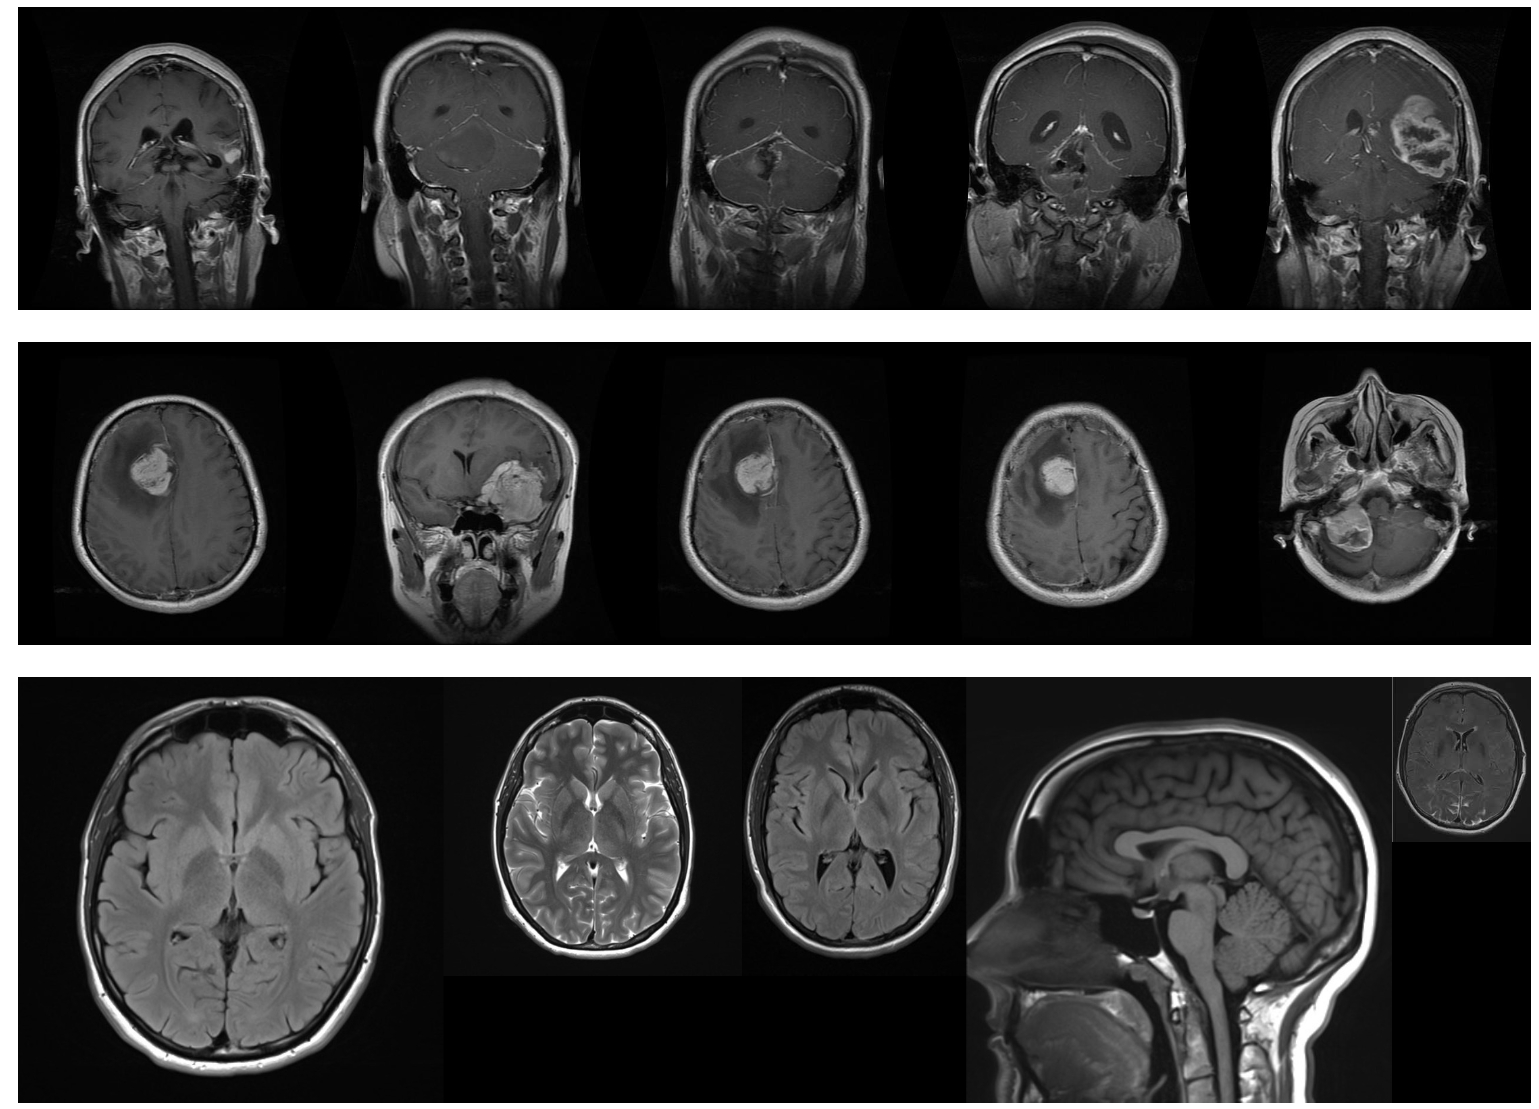

In this section, we use COAT to analyze unstructured data from three real-world scenarios: (1) brain tumor detection with MRI images (Bhuvaji et al., 2024), where COAT elicits visual factors; (2) climatic reanalysis data with fine-grained time and space coverage (Compo et al., 2011), where COAT writes code to interact with a database. (3) three-year news summary about one stock from the New York Times (Innovations, 2023), where COAT is applied to analyze the sequential data.

6.1 Eliciting Tumor-related Factors from Brain MRI Images

In this section, we utilize the COAT to explore the image dataset. Magnetic Resonance Imaging (MRI) is an important technique for detecting tumors in the human brain. The images are from an open Kaggle dataset (kaggle/brain-tumor-classification-mri) with an open-sourced project. (Bhuvaji et al., 2024). Each sample is a scanning MRI of a human brain. In this case study, the interesting variable is the tumor type. We consider three types of MRI images: glioma, meningioma, and no tumor. We include 20 images for each category and the total sample size is 60.